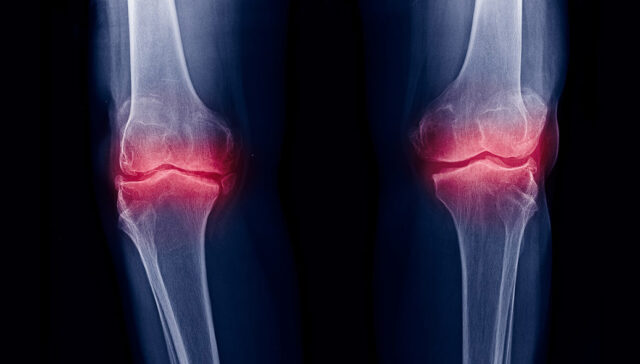

Em alguns pacientes, testes clínicos específicos não deixam dúvidas quanto à lesão. Em situações mais complicadas para identificar o problema, a ressonância magnética poderá confirmar ou não o diagnóstico.

Mais do que isso, a ressonância magnética ajuda a identificar lesões associadas nos meniscos, cartilagem ou outros ligamentos que precisem ser tratados junto com a ruptura do LCA.